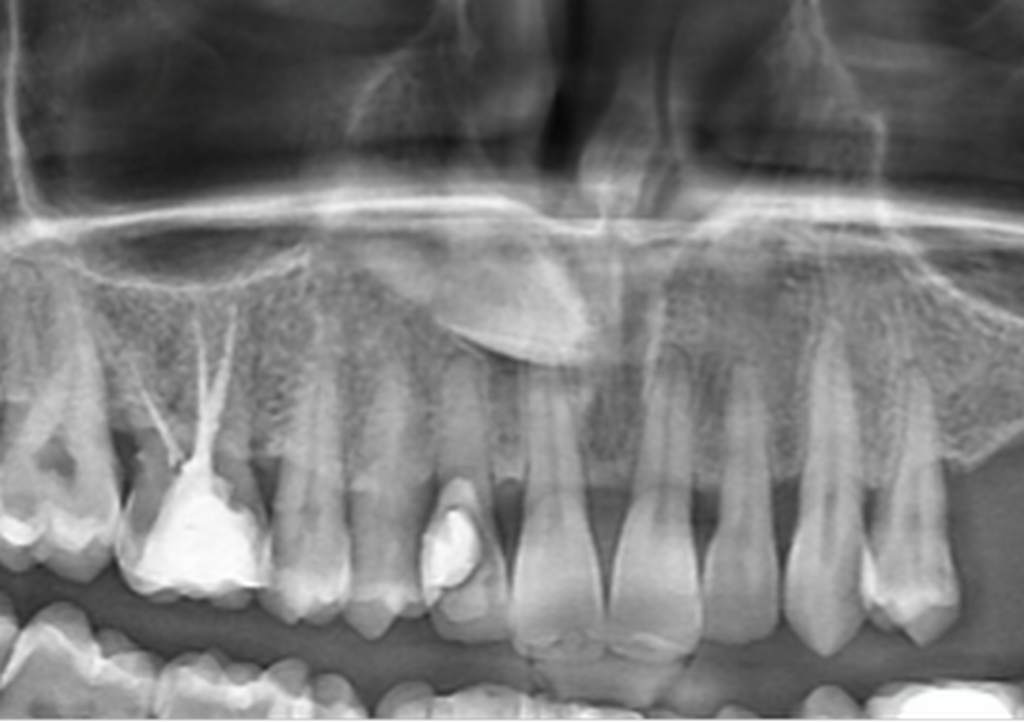

Ατελής ενδοδοντική θεραπεία που οδήγησε σε περιακρορριζική καταστροφή.

Η επανάληψη της ενδοδοντικής θεραπείας δεν οδήγησε σε πλήρη επούλωση της βλάβης,

καθώς είναι αναγκαία και η περιοδοντική θεραπεία του δοντιού.

Χρόνια φλεγμονώδης περιακρορριζική βλάβη, κυρίως,

λόγω ενδοδοντικής αιτιολογίας. Μετά την ενδοδοντική θεραπεία

ακολούθησε περιοδοντική θεραπεία.

Δύο χρόνια μετά, παρατηρείται πλήρης εξαφάνιση της βλάβης.